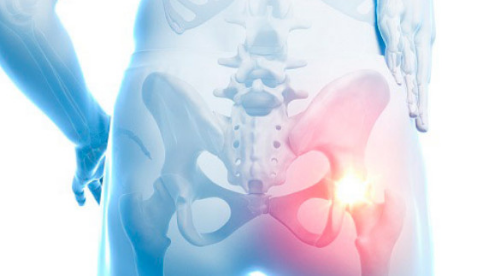

고관절 통증은 고관절과 관련된 관절 통증으로 정의됩니다. 이 관절은 상체에서 체중을 분산시키는 역할을 담당하며, 걷거나 뛸 때에는 체중의 약 3배나 10배가량의 부하를 견딥니다. 다른 관절과 마찬가지로 충격이나 체중 변화가 고관절 통증 증상을 유발할 수 있습니다. 이러한 통증 증상을 일으키는 주요 질환으로는 퇴행성 고관절염, 대퇴골 골절 그리고 선천성 고관절 탈구 등이 있습니다.

고관절은 골반과 대퇴골의 대퇴골두가 만나는 관절로, 상체와 하체를 연결하는 중요한 부위입니다. 이 관절은 서 있거나 앉아 있을 때부터 평소 일상생활에서 빈번하게 활용되는데, 이로 인해 상당한 부담을 견뎌내야 합니다. 고관절은 탁구공과 비슷한 크기와 모양을 가진 대퇴골두가 지탱하는데, 걸을 때 고관절에 가해지는 무게는 체중의 3~4.5배까지 증가하며 만약 계단을 오를 때는 대퇴골두가 체중의 8배에 달하는 부담을 견뎌야 하므로, 고관절은 상당한 스트레스와 손상의 위험에 노출될 수 있습니다.